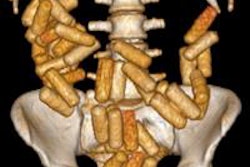

Top left: Low-dose linear slit digital radiography (LSDR) of a typical body packer with 145 intracorporal packs along the alimentary tract. Bottom left: Magnified view of the packs. Note the radiolucent rim within the periphery of the packs due to air trapping creating the so-called "double-condom sign" and "halo sign." Top right: DR of a typical body packer with 83 cocaine packs in the gastrointestinal tract. Bottom right: Note the longitudinal packs (weight approximately 10 to 12 g) projecting over the colon. The magnified view depicts the typical "double-condom sign" due to inevitable air trapped within the wrapping layers during manufacture.DR and low-dose linear slit digital radiography exams were less accurate. CT exams had an overall accuracy rate of 97.1%, followed by DR (71.4%, and 60% for low-dose linear slit digital radiography).